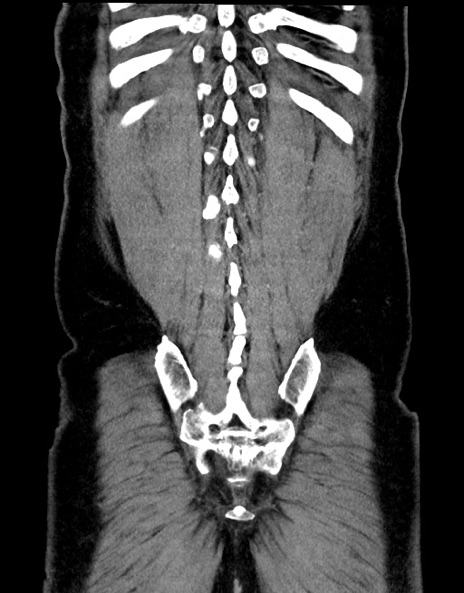

症例15(冠状断像)

症例

【症例】70歳代男性

【主訴】腹痛

【現病歴】今朝から腹痛あり。全体的に痛い。特に左上の方。排ガスが今日はない。冷や汗が出る。

【既往歴】直腸癌術後

【身体所見】左側腹部〜上腹部に圧痛あり。腹膜刺激症状明らかなではない。軽度反跳痛。左下腹部に術後瘢痕あり。

【データ】WBC 7700、CRP 0.02